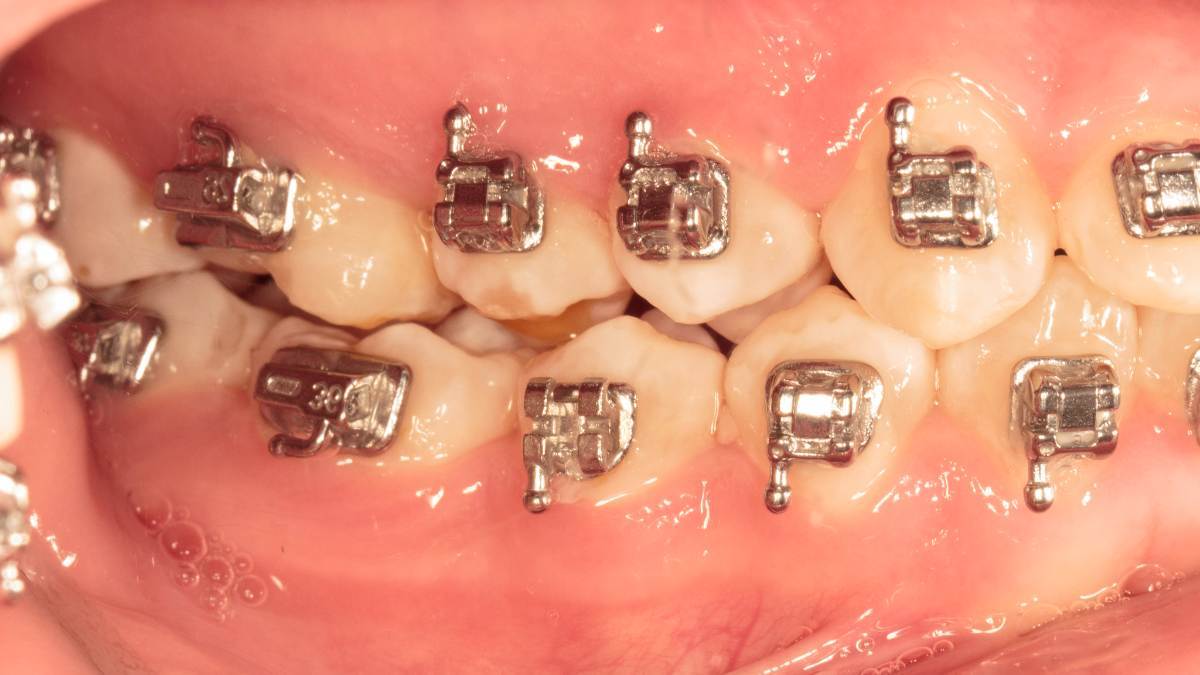

Женька Опубликовано 28 ноября, 2025 Поделиться Опубликовано 28 ноября, 2025 Всем привет, коллеги! 14 лет, терапевты ставят трещину по КТ (снимков до, к сожалению нет, косяк, каюсь). чуть сепарировав зуб и глянув на зуб под отлетевшим куском пломбы трещина "подтвердилась". Кейс на фото. Из интересного - маленький реколл в 1.5 года и спокойное перемещение зуба брекетами! 4 1 2 Ссылка на комментарий

Женька Опубликовано 17 декабря, 2025 Автор Поделиться Опубликовано 17 декабря, 2025 @сирена вот и завтра наступило) прощу прощения, что так долго, всё из головы вылетало на работе посмотреть. Пересадили в конце мая, к ортодонтии подключили в начале сентября ~3.5 месяца прошло с пересадки на тот момент. 1 Ссылка на комментарий